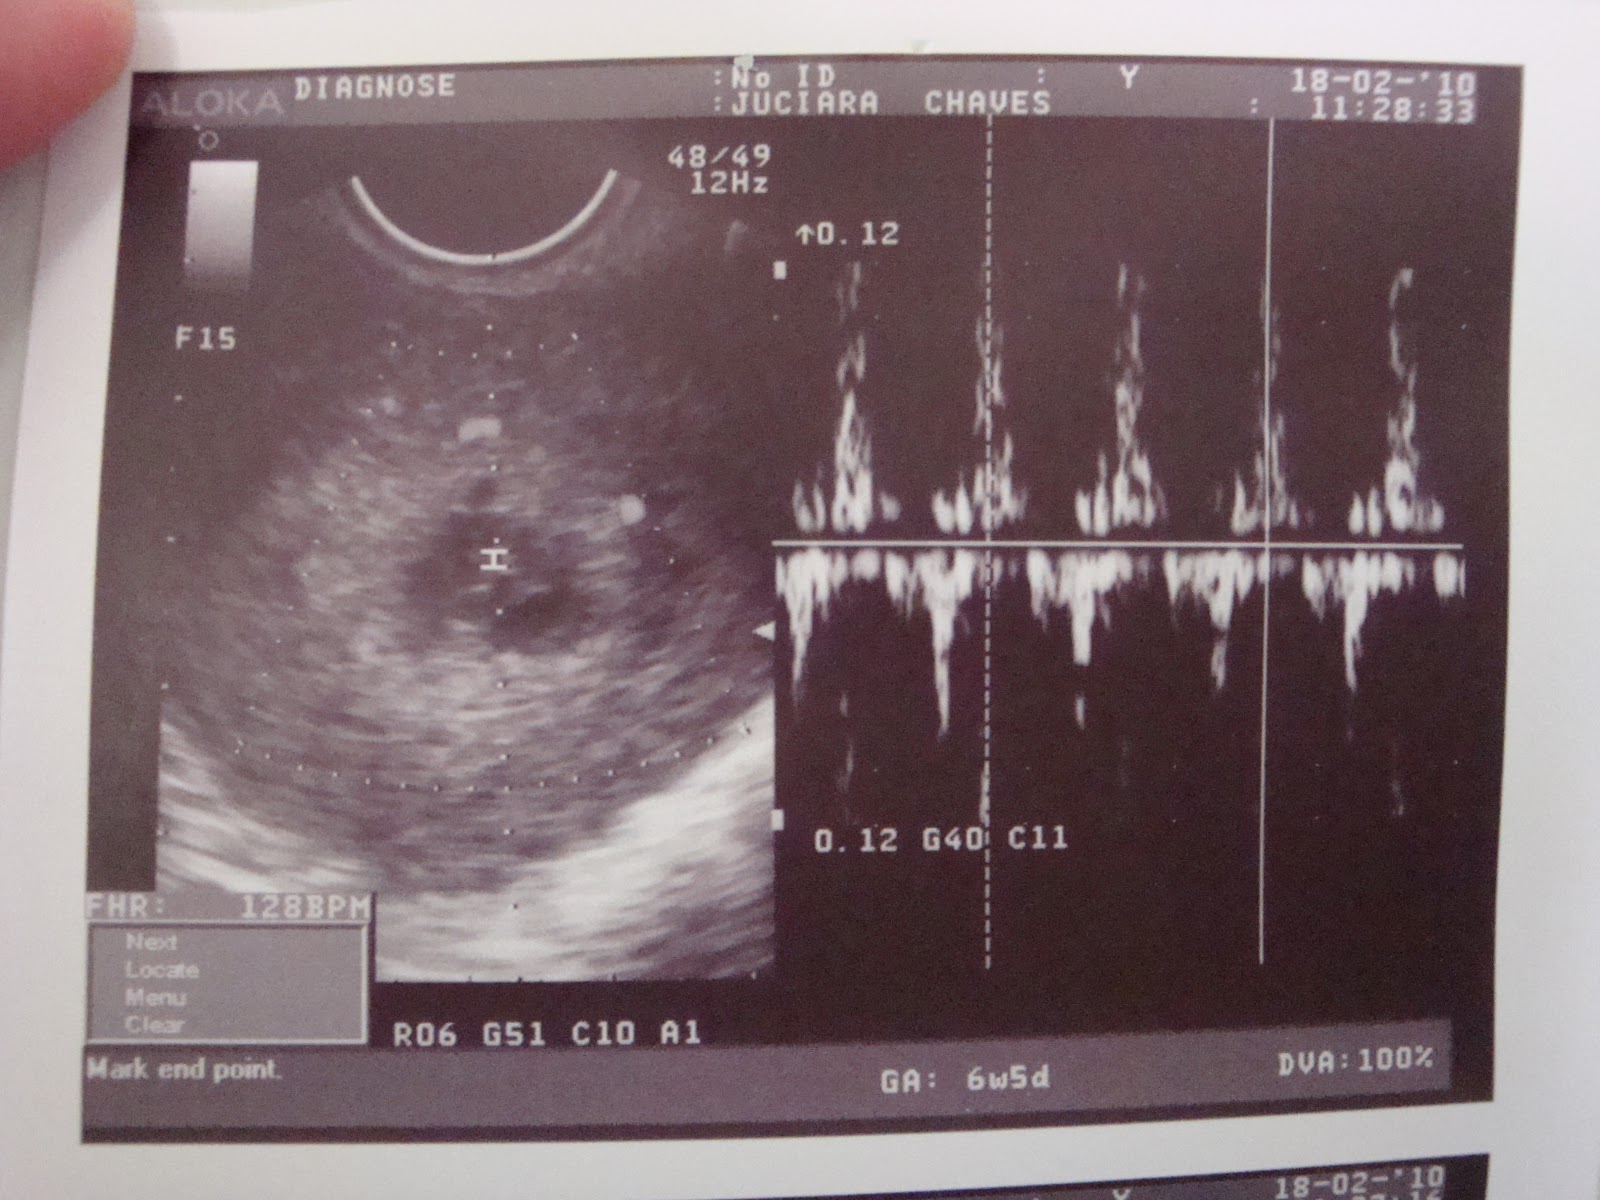

Ao retornar a Jequié em dezembro de 2001, começou o preparo para o exame da OPBB (Ordem dos Pastores Batistas do Brasil), que sendo aprovado, foi consagrado em culto de Ação de Graças no dia 15 de Abril de 2002. Logo em seguida seguiram-se os planos de casamento com a jovem Juciara Chaves, que a conhecia desde 1995 apenas como amigos, desde 1998 como namorados, desde 2001 como noivos e finalmente como casal desde 03 de agosto de 2002. Dessa união ainda não existem descendentes, mas existe um amor que cresce a cada dia que a convivência os proporciona uma harmonia de vida.